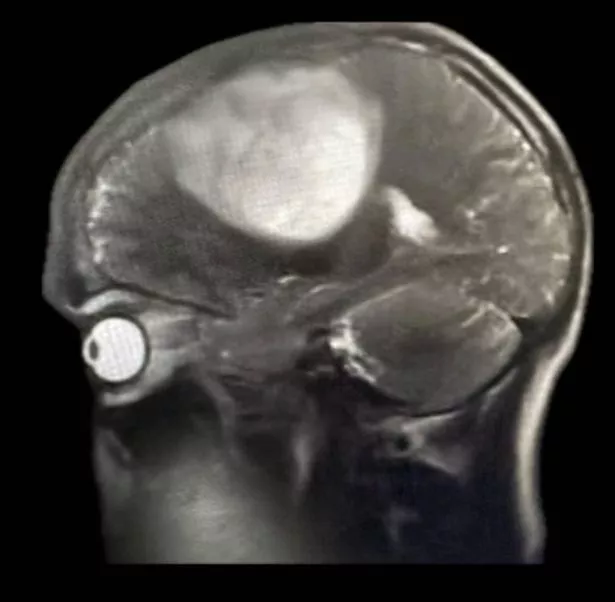

He said: “I was told I have two brain tumors – a large one on the right side of my head which was described as the size of a tennis ball and another smaller one the size of a squash ball in the middle.

“I was later told the bigger one might have been growing for 20 years and only now it has gotten so big it was pushing my brain and causing symptoms.”